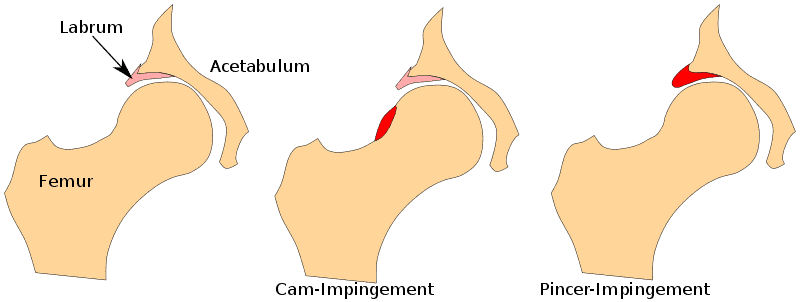

股骨髋臼撞击症(FAI)又称髋关节撞击症,是指髋臼和/或股骨颈的形态发生变化,导致髋关节在运动过程中撞击髋关节盂唇。 我们可以将其分为两大类: 当股骨头过大时,我们所说的是 CAM 形态(在男性中更为常见),而髋臼边缘过度伸展则被称为钳形形态,在女性中更为常见。 在混合型中,既有 CAM 形态,也有钳形形态。